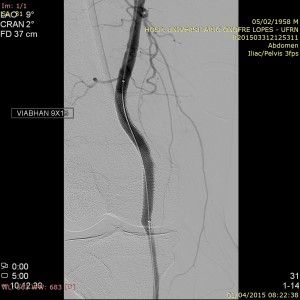

O tratamento escolhido foi o implante de stent revestido 7×40 devido ao menor calibre da artéria poplítea distal ao aneurisma. Contudo, o stent apresentou endoleak mesmo após a acomodação com balão 7×40. Assim, um stent mais calibroso e longo (9×15) foi implantado a partir da secção mais dilatada do stent 7×40, tendo eliminado o endoleak e excluído o aneurisma.

Após o procedimento o aneurisma foi completamente excluído e o paciente apresentou alívio gradual dos sintomas encontrando-se em controle ambulatorial.